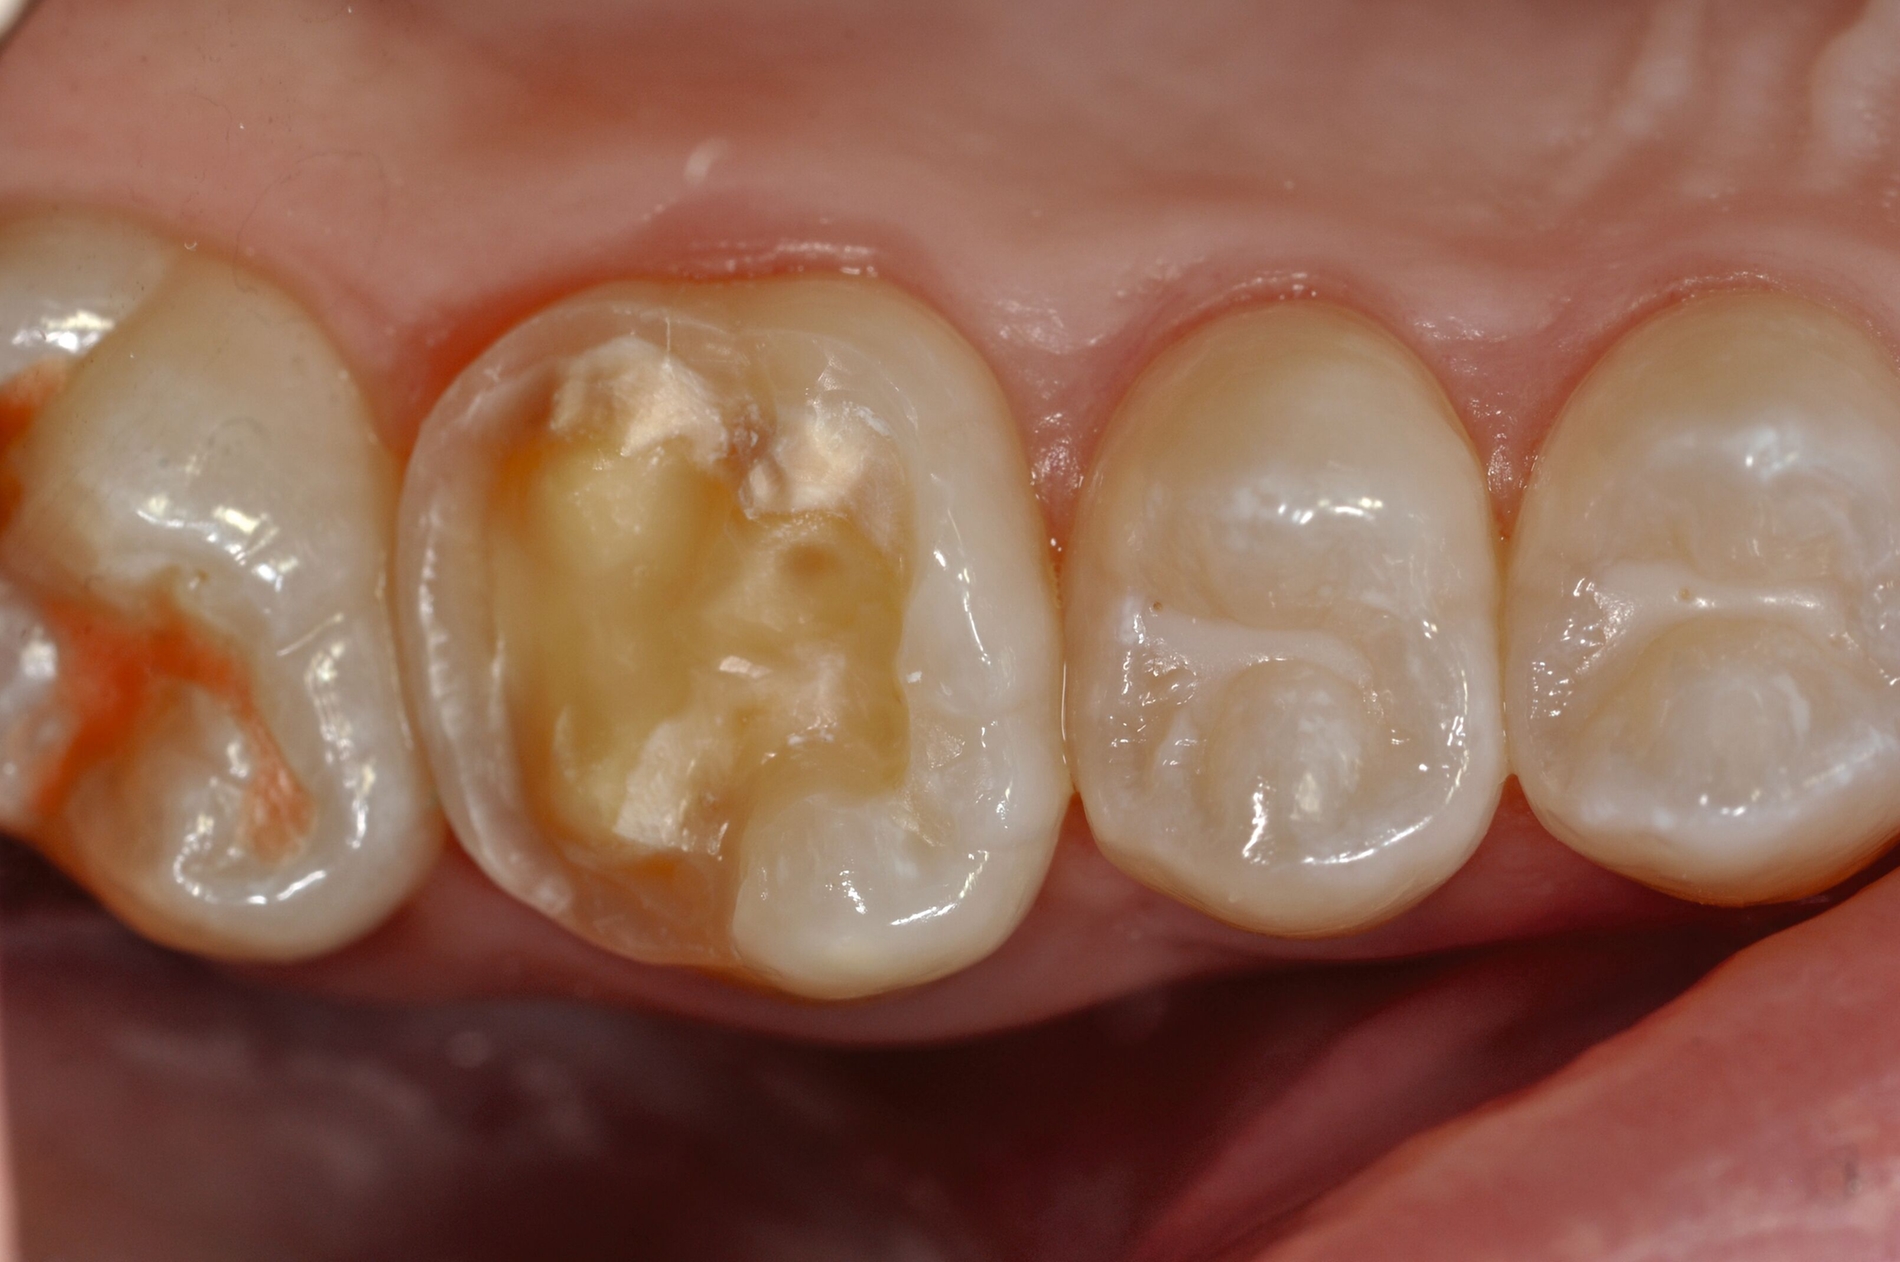

Diese Klassifikation dient als Grundlage für die Therapieempfehlungen. Deutlich wird, dass aufgrund der Symptomatik die Therapie der Zähne höchst unterschiedlich ausfällt. Dass etwa eine Opazität ohne Überempfindlichkeit (Index 1, Abbildung 1) ein anderes therapeutisches Vorgehen erfordert als ein Zahn mit nahezu komplettem Einbruch der Zahnoberfläche und mit Hypersensitivität (Index 4, Abbildung 2), ist offensichtlich.

Die Therapie C hat das Ziel, MIH-Zähne vorübergehend zu versorgen, bis der vollständige Durchbruch der Zähne eine adhäsive Restauration ermöglicht, um die hypersensiblen Zähne zu desensibilisieren oder/und die Mitarbeit für die weitere Behandlung aufzubauen. Vor dem Hintergrund des erhöhten Kariesrisikos dieser Zähne (Abbildung 2) muss durch die Maßnahmen eine Kariesprogression vermieden werden.